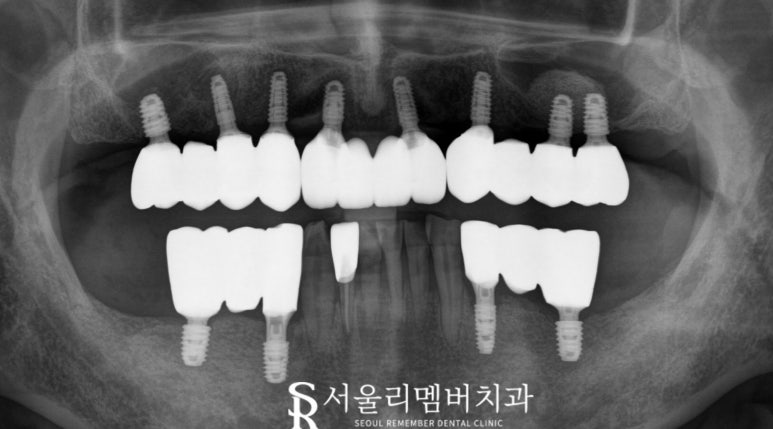

구강 모습을 보니 아랫니 몇 개와 윗니 하나를

제외하고는 거의 치아가 없는 모습인데요,

더 자세히 알아보기 위해 사당 치과 에서는

엑스레이와 CT 사진을 통해

구강 구조를 면밀히 분석했습니다.

이를 통해 뼈의 상태, 잇몸의 건강 등을 확인하고,

식립 위치를 계획했습니다.

엑스레이 사진에서도 문제없이

뼈에 잘 식립된 모습을 확인했습니다.